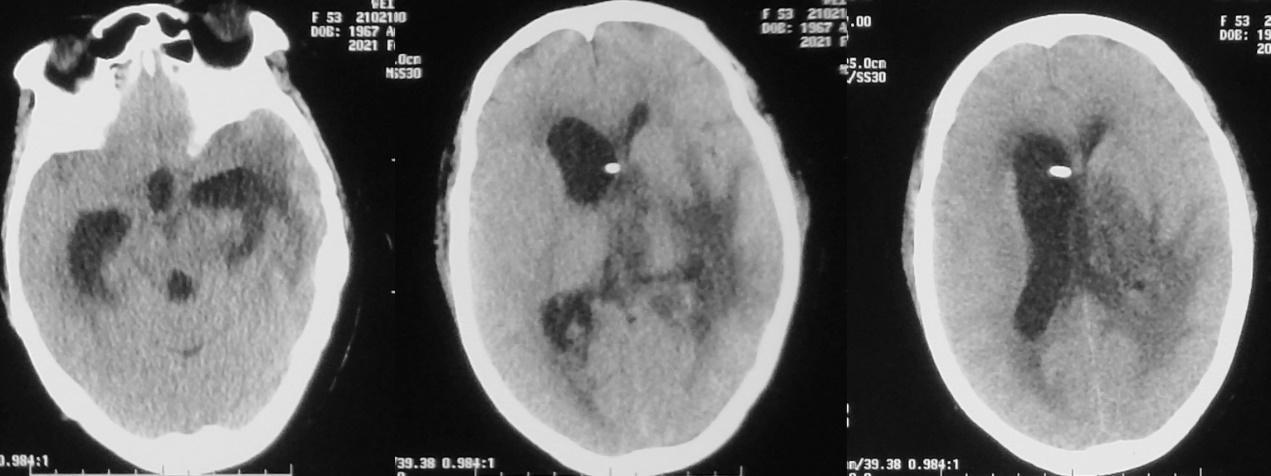

脓肿清除术后第3天,颞角外引流术后第2天即2020年12月10日,意识仍呈朦胧状态,刺激睁眼,简单配合动作,复查头颅CT呈术后改变,但右侧脑室 较前明显扩张( 图-12); 当天行加行右侧脑室穿刺外引流术。

图-12: 2020年12月10日头CT

脓肿清除术后第5天,颞角外引流术后第4天,右侧脑室穿刺术后2天,即2020年12月12日上午,意识进一步变差,呈浅昏迷状态,复查头颅CT( 图-13 )见脑室缩小,但术区水肿明显;当天下午意识又有恶化,再次复查头颅CT( 图-14 )见术区水肿明显加重,转入ICU进一步治疗,并于当天进行了气管切开术。

图-13: 2020年12月12日上午头CT

图-14: 2020年12月12日下午头CT

经治疗后患者病情稍好转,可自动睁眼,刺激肢体可活动。左侧脑室引流管因无引流液流出,于脓肿清除术后7天,即2020年12月15日给予拔除。

脓肿清除术后第8天,左侧颞角外引流术后第7天,右侧脑室穿刺术后5天,即2020年12月16日复查头颅CT见术区出血开始吸收,但水肿仍明显,脑室无扩张( 图-15 )。

图-15: 2020年12月16日头CT